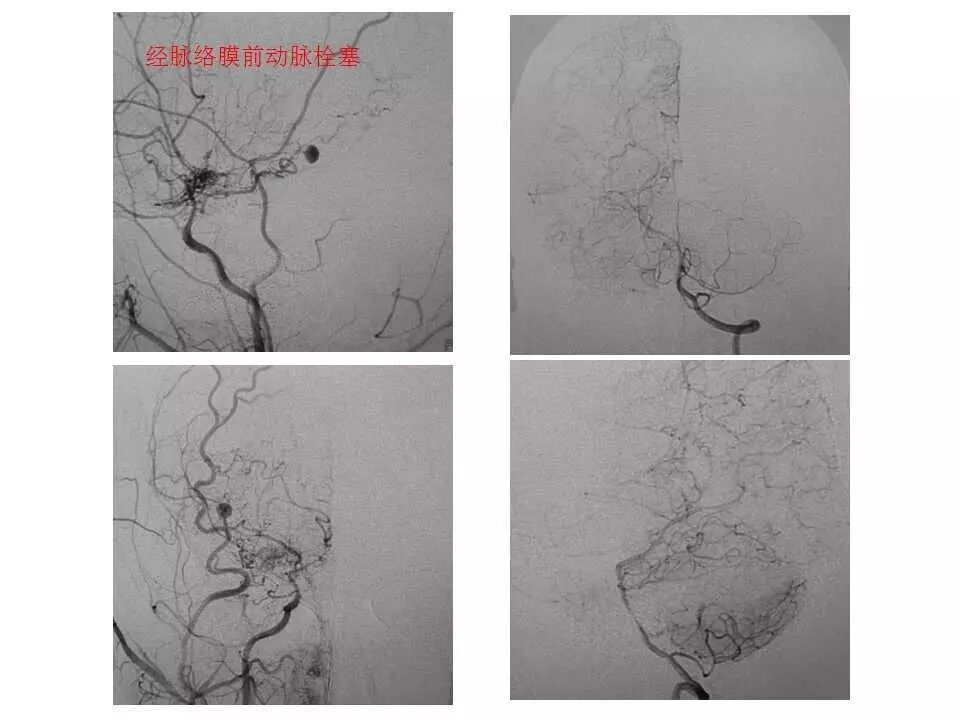

今天为大家分享的是“强生医疗CNV-神经介入专栏”第十五期,由首都医科大学宣武医院何川教授带来的“颅内动脉瘤介入治疗”精彩讲课视频及PPT,欢迎观看、阅读。文章仅代表作者个人观点,如有不同见解,欢迎同道斧正!

何川 ,首都医科大学宣武医院副主任医师,中国医师协会神经介入专业委员会常务委员,长期从事脑血管病和脊髓血管病的手术及介入治疗和相关研究工作。首都医科大学神经外科博士,师从于中国神经介入开创人凌锋教授;日本东北大学医院脑血管病治疗科博士后,师从于日本国脑血管病血管内治疗的开创者高桥教授。